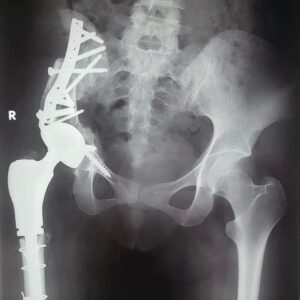

في إجراء أول جراحة من نوعها لاستئصال ورم من عظمة الآلية ومفصل الحوض؛ لفتاة تبلغ من العمر الخامسة عشر وتركيب مفصل صناعي كامل للحوض؛ مما يمثل إضافة جديدة إلى سجل نجاحات مستشفيات جامعة أسيوط المشهود لها، وتميُّز كوادرها الطبية

مبيناً أنه تم إجراء عملية إزالة للورم واستئصال العظم المصاب بالسرطان ونقل الجزء العلوي من عظمة الفخذ لتحل محل عظمة الآلية

أن المريضة تبلغ من العمر 15 عامًا ، وكانت تعاني من وجود ورم في عظمة الآلية، ومفصل الحوض مشيرًا إلى إجراء العملية الجراحية على مرحلتين في إطار زمني 3 شهور لتجنب البتر

حيث تم في المرحلة الأولي إزالة الورم من عظمة الآلية، ونقل الجزء العلوي من عظمة الفخذ ؛ لتحل محل عظمة الآلية.

أنه تم بعد إجراء الفحوصات الطبية تركيب مفصل صناعي كامل ذي مواصفات خاصة للحوض، وذلك دون اللجوء لتثبيت المفصل، ولتجنب البتر لهذا الطرف مشيرًا إلى نجاح العملية، واستقرار الحالة الصحية للمريضة، وتمت متابعتها لحين عودة حركة المريضة لصورتها الطبيعية، ومشيرا في الوقت نفسه، أنه تم نشر العملية الجراحية عالميًا في مجلة علمية متخصصة للحالات الصعبة بمساعدة الدكتور أحمد عادل خليفة مدرس جراحة العظام بكلية طب قنا جامعة جنوب الوادي.